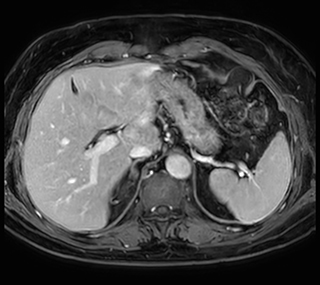

Ascites can be hard to image, but excellent result is obtained with Ingenia Ambition. This high resolution image demonstrates the high quality that can be obtained with VitalEye and the patient just breathing normally. The acquisition time is fast thanks to the accuracy of the respiratory gating with VitalEye** and it also saves the time needed to put a respiratory belt on the patient.

3D T2 with VitalEye